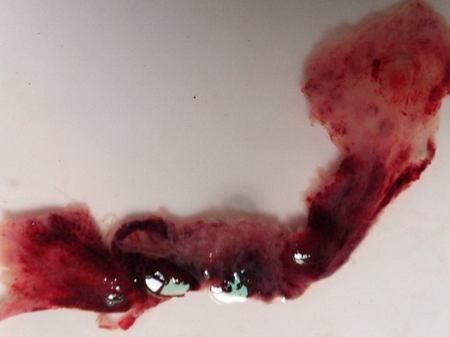

孕囊掉落是指懷孕初期,由于某些原因,孕囊與子宮壁分離并排出體外的過程,這種情況通常伴隨著出血和腹痛等癥狀。

許多準(zhǔn)媽媽都經(jīng)歷過孕囊掉落的情況,在這一過程發(fā)生時(shí),準(zhǔn)媽媽可能會(huì)感到腹部不適、出血等癥狀,隨著孕囊的排出,這些癥狀會(huì)逐漸減輕。

為了更好地理解孕囊掉落的過程,我們分享一些相關(guān)的圖片(此處可插入孕囊掉落的圖片),這些圖片可以幫助讀者直觀地了解孕囊的外觀、大小以及排出過程。